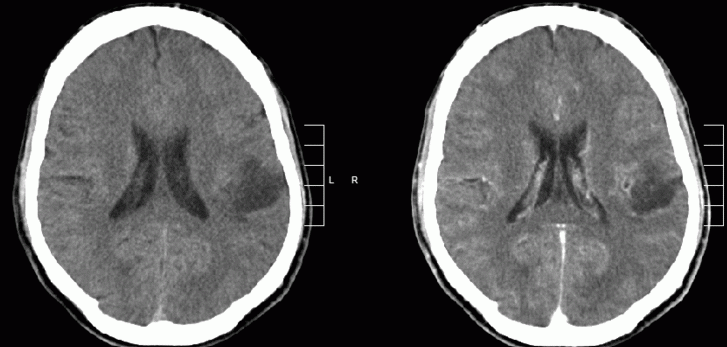

胶质瘤鉴别诊断

潜在的差异可以是肿瘤或非肿瘤性病变。肿瘤性病变包括脑膜瘤、继发性转移或淋巴瘤,而肿块性病变的非肿瘤性原因包括感染(即脑脓肿)或梗塞。